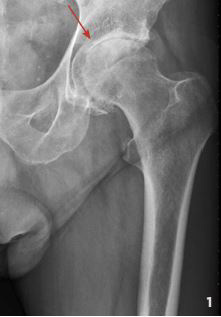

Die generelle Indikation für ein künstliches Hüftgelenk ist gegeben, wenn neben der bildgebend gesicherten Diagnose (z.B. hochgradige Arthrose oder Minderdurchblutung des Hüftkopfs) eine relevante subjektive Einschränkung der Lebensqualität vorliegt. Die Betroffenen leiden unter starken Schmerzen und einer Beeinträchtigung ihrer Mobilität, die sich mit Medikamenten und Physiotherapie nicht mehr behandeln lassen (vgl. Abb. 1).

Abb. 1

Röntgenbild eines Hüftgelenks mit Arthrose.

Der Gelenkspalt (siehe Pfeil) ist aufgrund

des Knorpelabbaus verschmälert, und die

Knochen reiben schmerzhaft aufeinander.